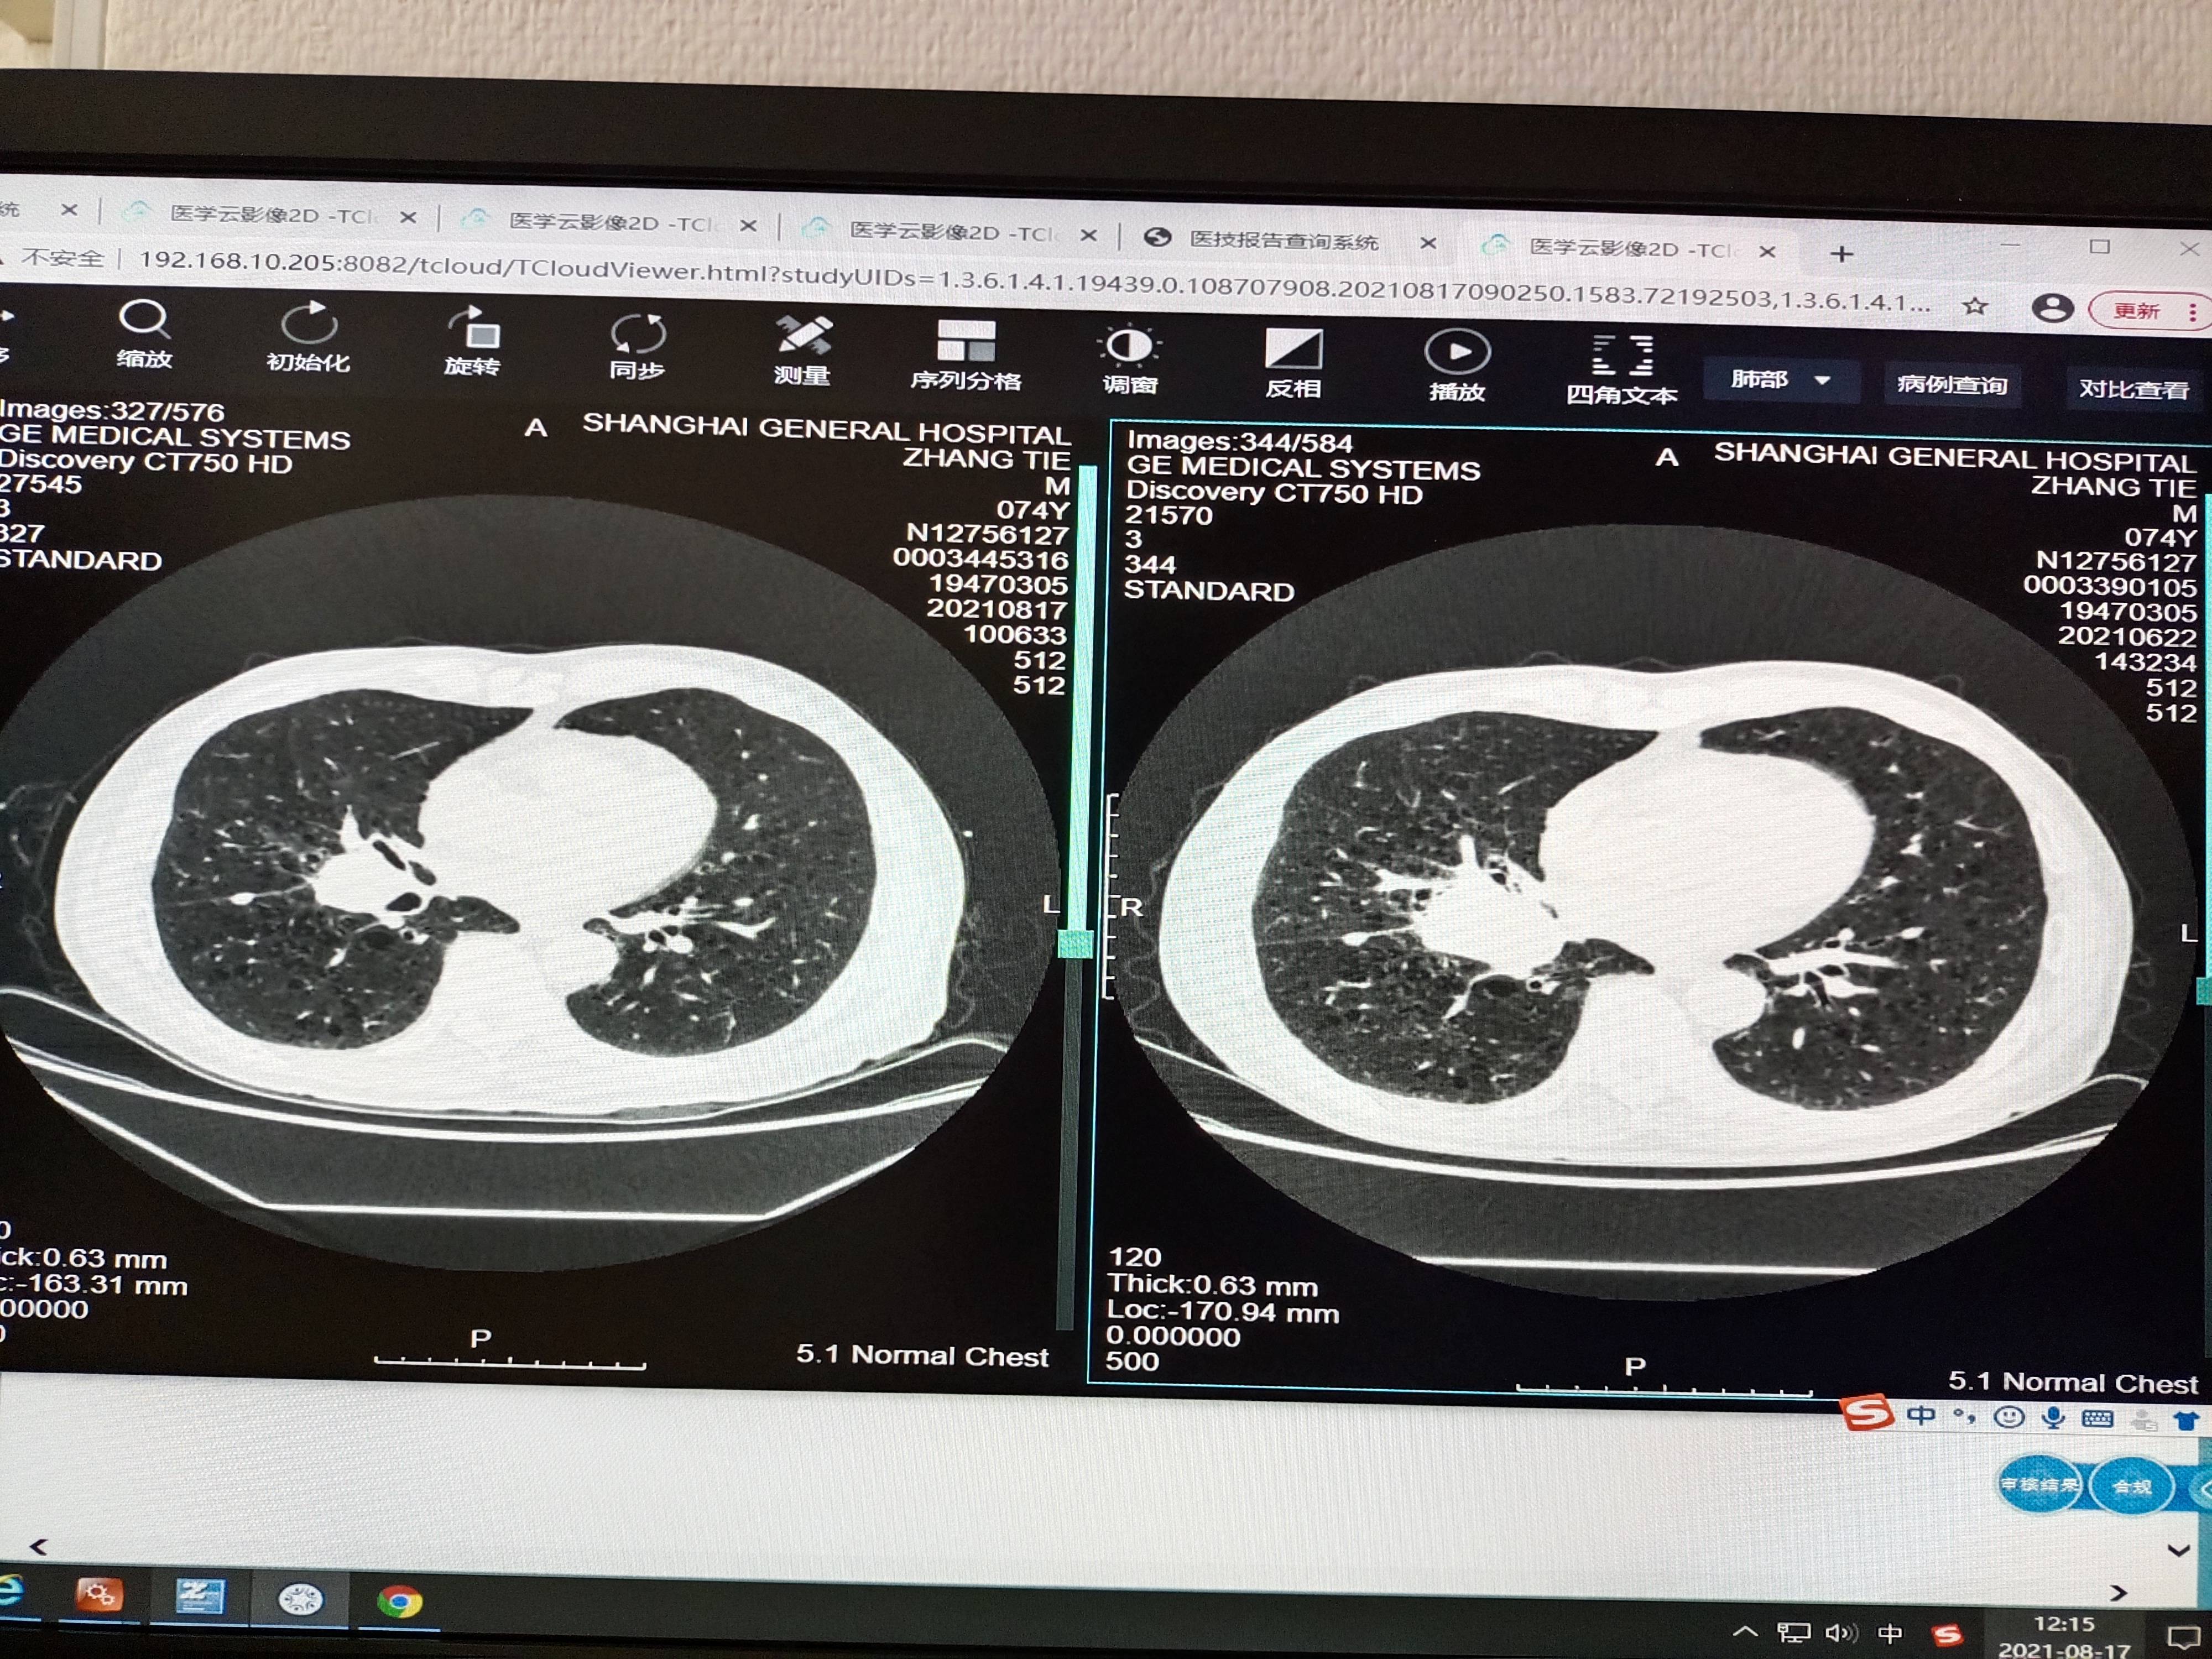

不知不觉昨天已经完成第四针的K药和恩度注射,6月22日第二针前CT显示肿瘤从7缩小到5.8。8月17日第四针前CT显示从5.8缩小到3.77。入院体检又胖了5斤,关键是胃口好,也没有特意去补。体感非常好,各项检查数据不错,心情很好,晚上观看了一场孙子的冰球比赛。一切向着好的方向发展,加油老爸